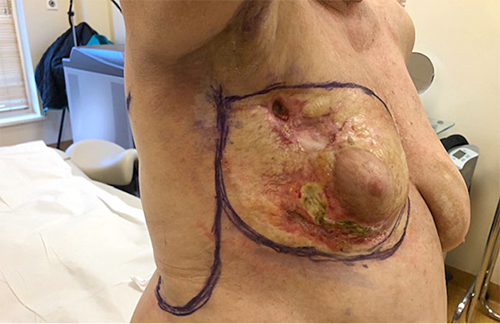

83 m. pacientė konsultuota dėl negyjančių gilių dešiniosios krūties žaizdų, keletą metų gydomų ambulatoriškai.

Prieš atsirandant negyjančioms žaizdoms, pacientės dešinioji krūtis operuota dėl pirminio krūties vėžio. Po operacijos kurį laiką savijauta buvo gera. Vėliau atsivėrė krūties žaizdos (žr. 1B pav.).

1B pav. Keletą metų gydoma išopėjusi dešinioji krūtis prieš operaciją

Pacientė ne kartą kreipėsi dėl palaipsniui atsiradusių negyjančių ir kalkėjančių dešiniosios krūties žaizdų, kurios kelia skausmą ir trukdo aktyviai veiklai. Nuolat atliekami rutininiai kraujo, rentgenologiniai ir kt. tyrimai nerodė nukrypimų nuo normos.

Įvertinus gerą pacientės fizinę būklę, ilgus metus nesugyjančias kalkėjančias skausmingas žaizdas, pacientei rekomenduotas operacinis gydymas.

2B pav. Priešoperacinis pjūvių planavimas

Planuotas radikalus kalcifikavusios krūties ir negyjančių žaizdų pašalinimas ir susidariusio defekto padengimas. Tam tinkamiausias metodas – pilvo apatinės dalies odos, poodžio ir tiesiojo pilvo raumens panaudojimas. Tačiau šios srities pacientės odai pakenkusi skleroderma, todėl nuspręsta panaudoti nepakenktos odos vietą iš krūtinės ir nugaros srities, formuojant dviskiltį pasukinį (rotacinį) lopą (žr. 2B pav.).